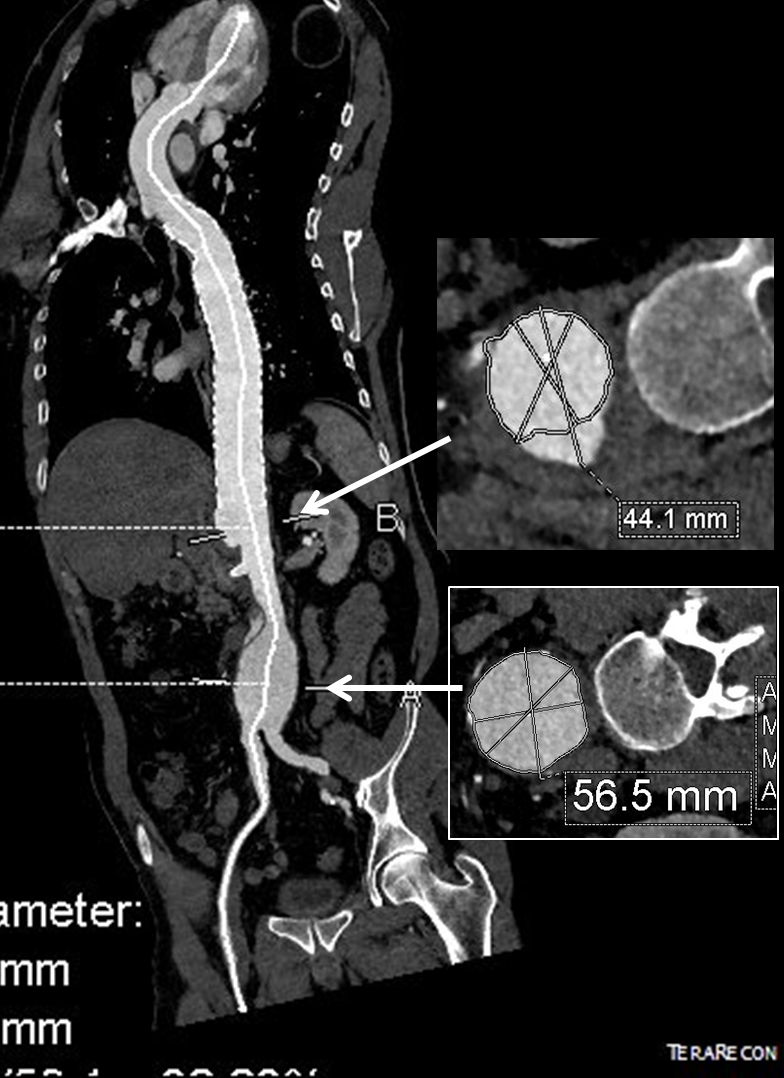

The patient is a middle aged man in his 50’s who presented with a type B aortic dissection. His dissection flap spanned from his left subclavian artery to the infrarenal aorta. He was a long time smoker and had hypertension that was difficult to control, made much worse after his dissection. He had a moderate dilatation of his thoracic aorta, maximally 36mm and tapering to 35mm in visceral segment. There was a 4.9cm infrarenal AAA where the dissection terminated.

His chest pain resolved with blood pressure control and he was discharged, but in followup his thoracic aortic segment grew and his blood pressure worsened, never getting below a 150mmHg systolic despite multiple agents. CTA two months after presentation, showed growth of his TAA to 44mm from 36mm in two months and the visceral segment showed that his dissection flap impinged on flow to the right renal artery. His AAA remained the same. He continued to have bouts of chest pain related to hypertension.

He at 6 month post TEVAR followup, CTA showed stablility in his thoracic aorta. in infrarenal AAA grew from 5.0 to 5.7cm between the 1 month CT and the 6 month CT.

The terminus of the stent graft excluded the false lumen in the thoracic aorta but also resulted in filling and pressurization of the false lumen beyond and can be seen as a 44mm lateral dilation of the visceral segment of the aorta which had developed in the 6 month interval since the TEVAR.

He did well in subsequent followup, having successfully quit smoking. He retired early on disability and was becoming more active, but the visceral segment dilatation was concerning. At 6 months post infrarenal AAA repair, he underwent CTA and it showed patent thoracic stent graft and infrarenal abdominal graft. The intervening visceral segment continued to enlarge and was now 46mm. The decision was to wait another interval 9 months to see if this would stabilize. The segment grew some more and was 49mm. He wanted to give it another 6 months and at that time, CTA showed further growth over 5cm, and he had developed some abdominal discomfort. He was taken to the operating room.